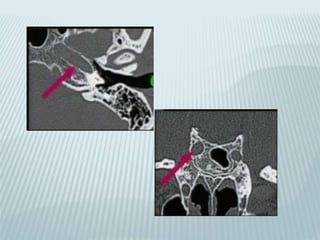

Posterior petrous aqueducts

Vestibular (endolymphatic):

parallel to petrous ridge

Cochlear (perilymphatic):

Verticaly below and parallel to

inner ear canal

VESTIBULAR AQUEDUCT

 10 mm long endolymphatic duct

 From common crus to post wall of petrous

pyramid

 Joins endolymphatic sac nestled in leaves of

dura

 Equilibration of endolymphatic fluid pressure

COCHLEAR AQUEDUCT

 8 mm long perilymphatic aqueduct

 From basal turn of cochlea to medial border

of jugular foramen

 Regulation of CSF and perilymphatic fluid

pressure